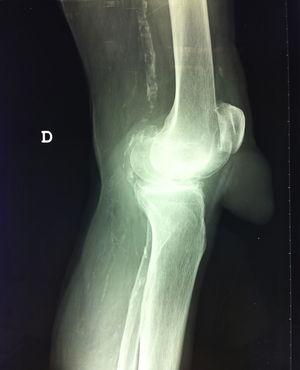

En la exploración física destacaba una tumoración de consistencia blanda de forma cónica con una circunferencia de base de 8cm y una altura de 6cm ubicada por delante del área correspondiente al tendón rotuliano. La tumoración era indolora, aparentemente no dependiente de planos profundos y no presentaba calor local. En su región distal se apreciaba una piel más delgada, violácea y descamada. La paciente señalaba dichos cambios como los que motivaron su consulta (fig. 1).

En una exploración radiológica de la rodilla se apreció que la tumoración era dependiente de partes blandas, no presentaba imágenes radioopacas en su interior y que respetaba la integridad del tendón rotuliano. Como otros hallazgos destacaba cierto grado de gonartrosis y la presencia de signos radiológicos de ateromatosis (fig. 2).